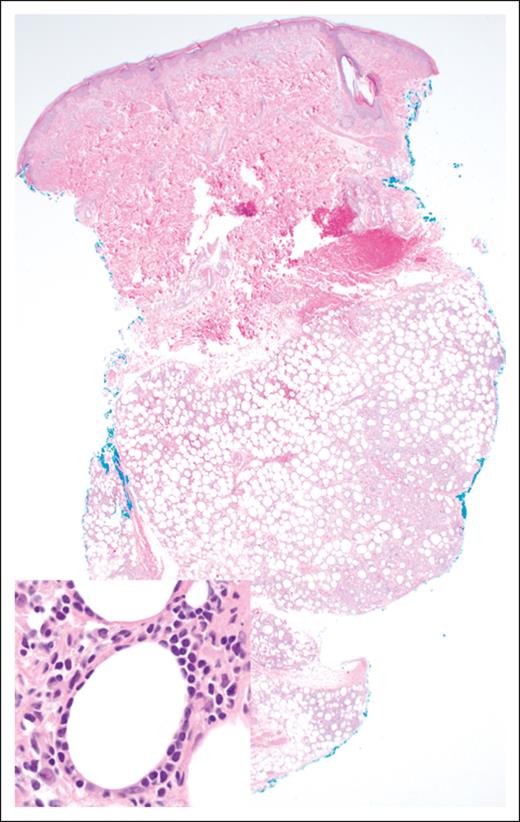

Morphologically, the malignant lymphocytes in SPTCL create a lobular panniculitis pattern with a characteristic rimming pattern around adipocytes68 (Figure 3). Most lesions feature small- to medium-sized cells, which are positive for CD8, TCR-βF1, and pan–T-cell markers CD2, CD3, CD5, and CD7 (with variable degrees of expression loss), along with cytotoxic markers TIA-1, perforin, and granzyme-B. CD30 and CD56 are negative, as is in situ hybridization for EBV encoded RNA. The proportion of proliferating cells as measured by antibodies to Ki-67 (eg, MIB-1) is high, and there is often a prominent histiocytic component, more pronounced in cases with necrosis.64,68 Although the molecular mechanisms underlying the predisposition for adipose tissue infiltration are not fully understood, the expression of CCR5 on malignant T cells and the secretion of its ligands from immunologically activated adipocytes (CCL3, CCL4, and CCL5) may contribute to the pathogenesis and clinical manifestations of SPTCL.69,70

SPTCL. The lobular subcutaneous infiltrate spares the overlying dermis and epidermis (original magnification ×20; H&E stain). Inset: the lymphoma cells display a characteristic rimming pattern around adipocytes (original magnification ×500; H&E stain).